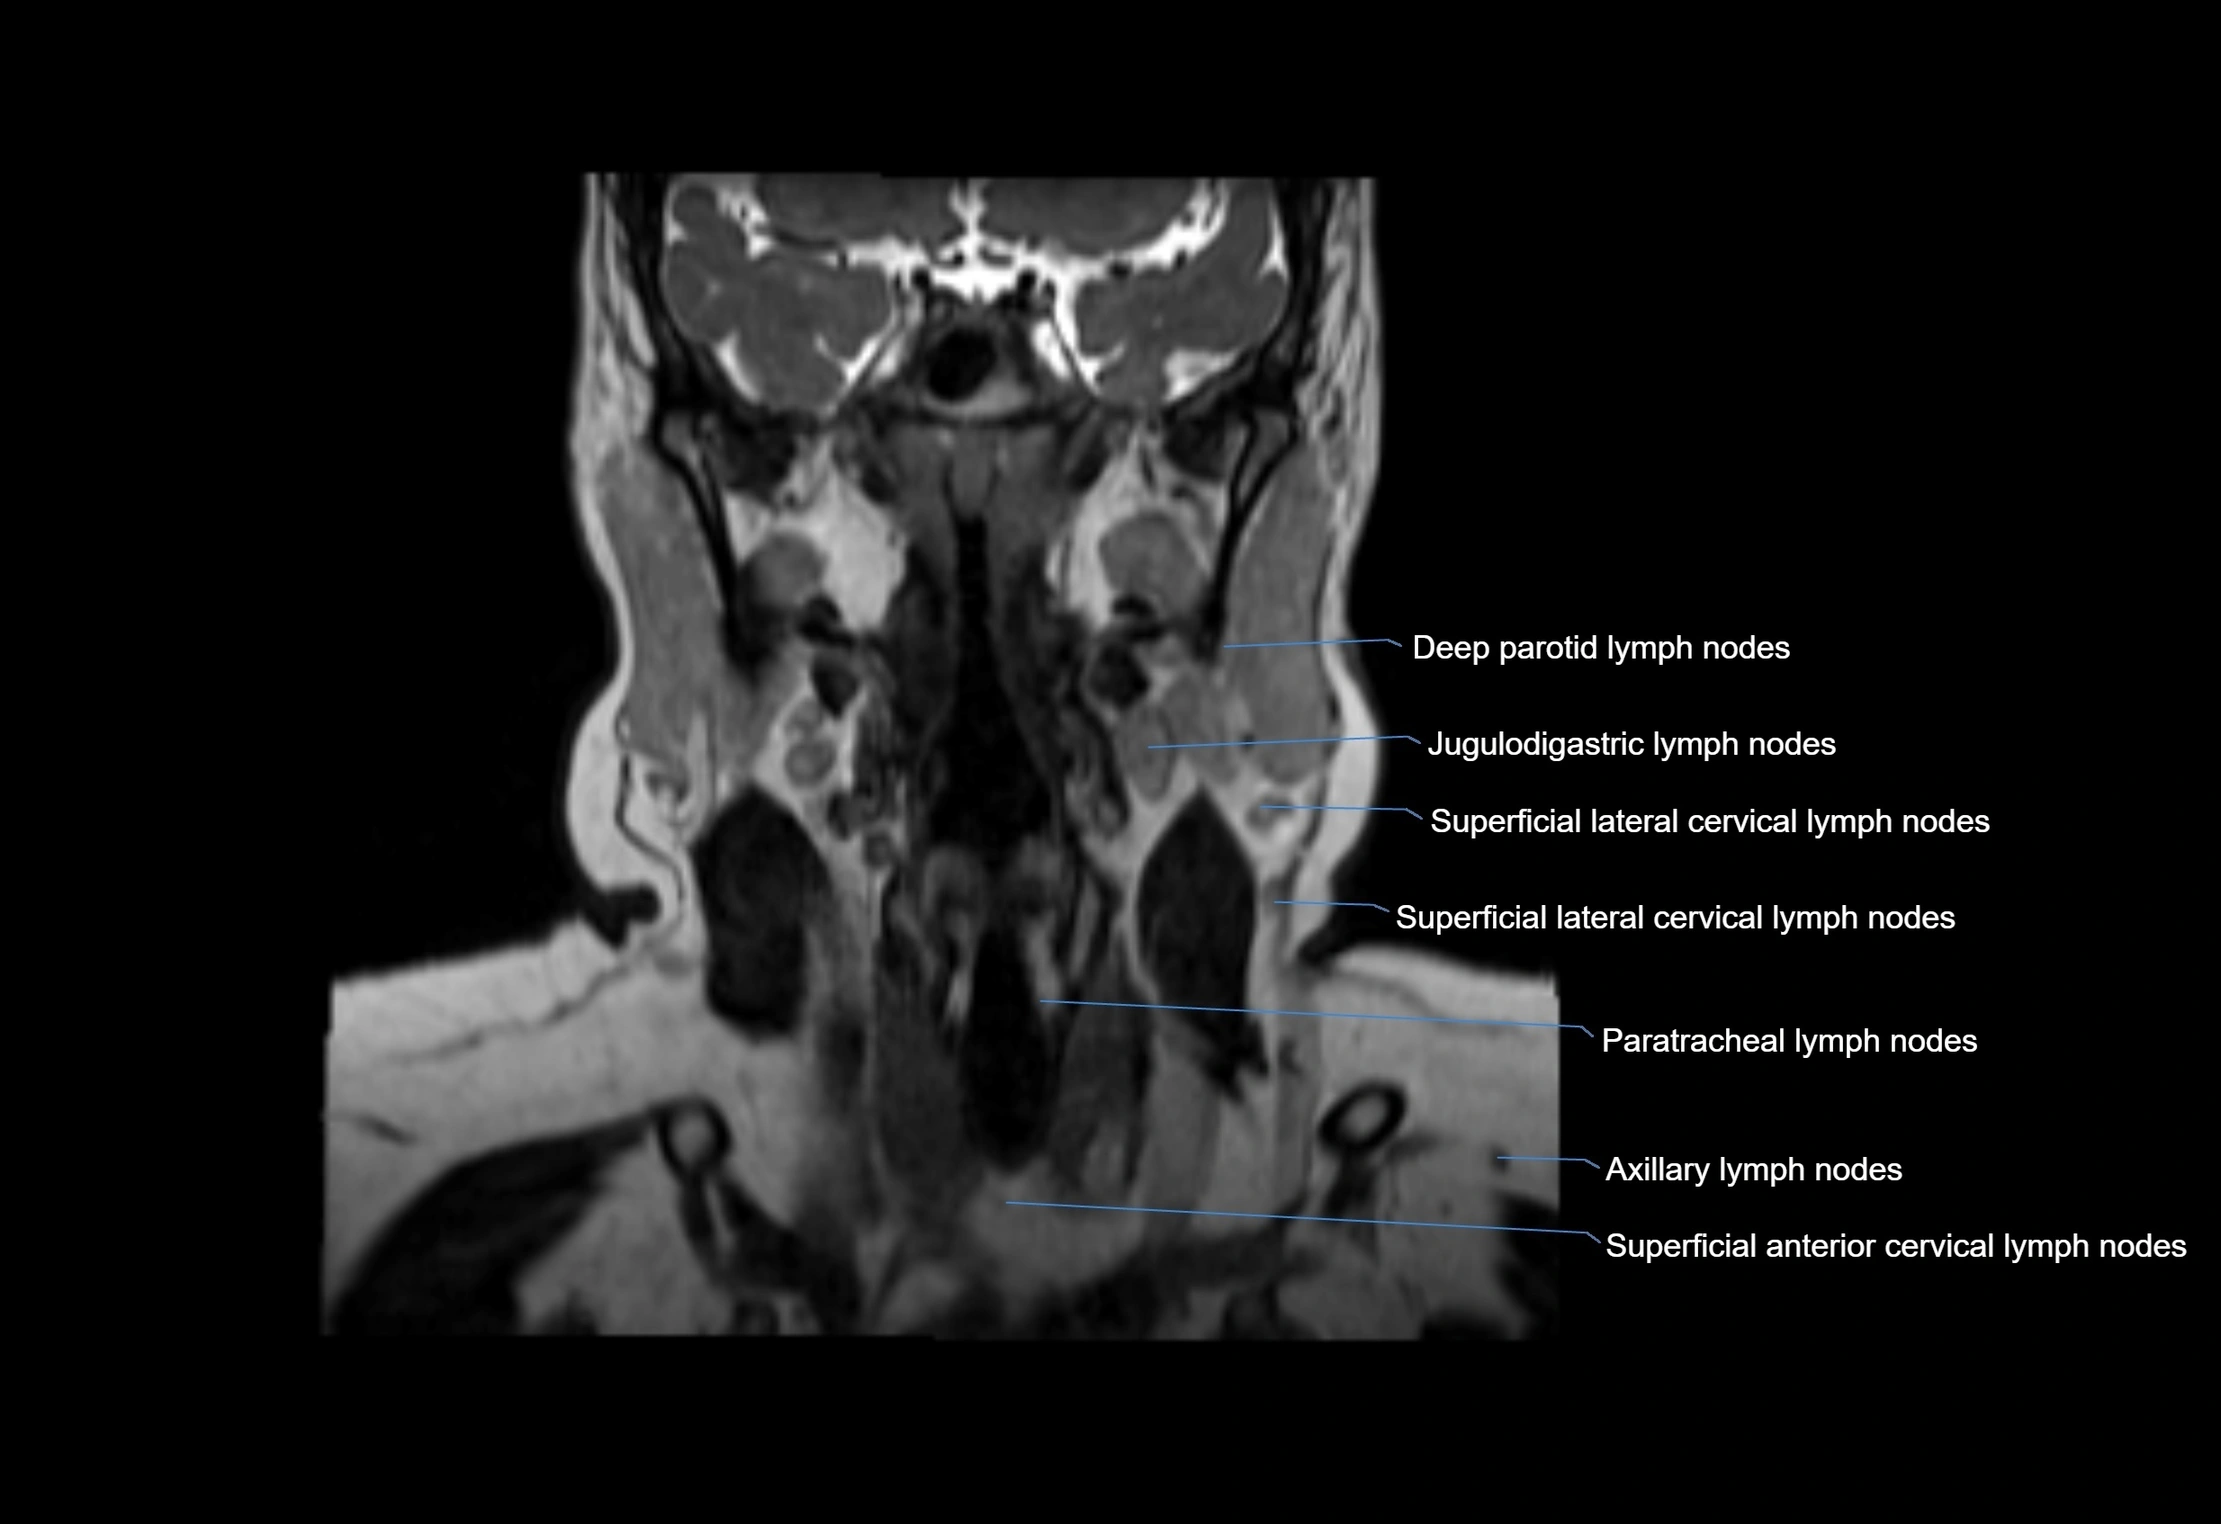

Location

• Found along primary lymph node chains, including preauricular, submandibular, parotid, and occipital regions

• Embedded in subcutaneous fat or superficial fascia, often lateral or posterior to primary nodes

• Variable in number; may occur unilaterally or bilaterally, depending on individual anatomy

CT Appearance:

• Nodes appear as small, soft tissue density structures embedded in subcutaneous fat near primary lymph nodes

• Surrounded by air in adjacent facial cavities or normal soft tissue, providing natural contrast

• Enlarged or pathological nodes appear as well-defined or irregular soft tissue masses

• CT is particularly useful for preoperative assessment, infection evaluation, or detection of metastatic spread